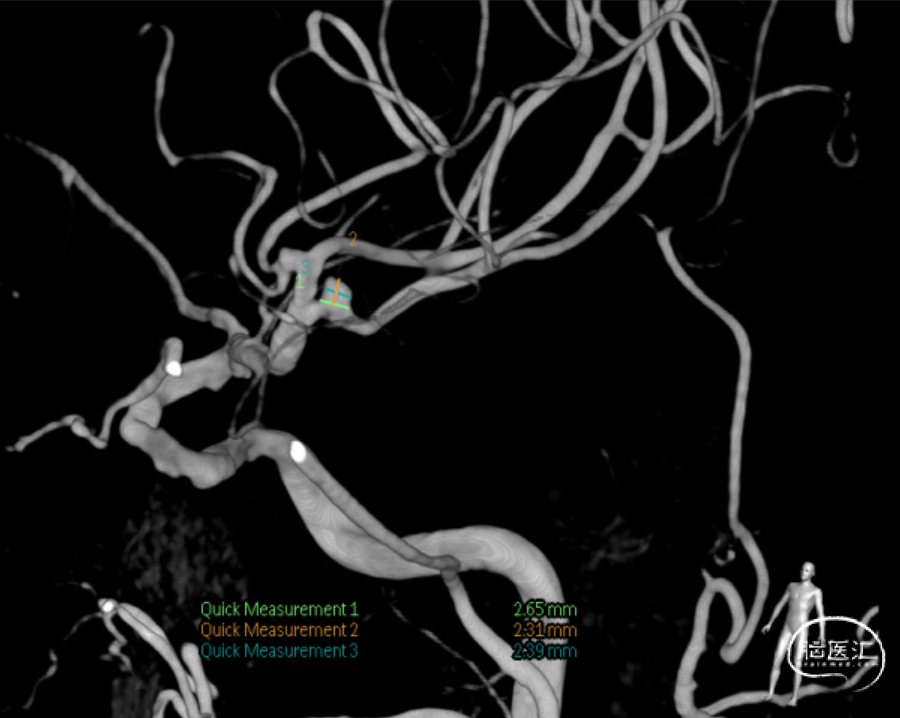

DSA提示左侧大脑中动脉瘤。瘤颈约2.65mm,大小约2.31mm*2.39mm*2.38mm。